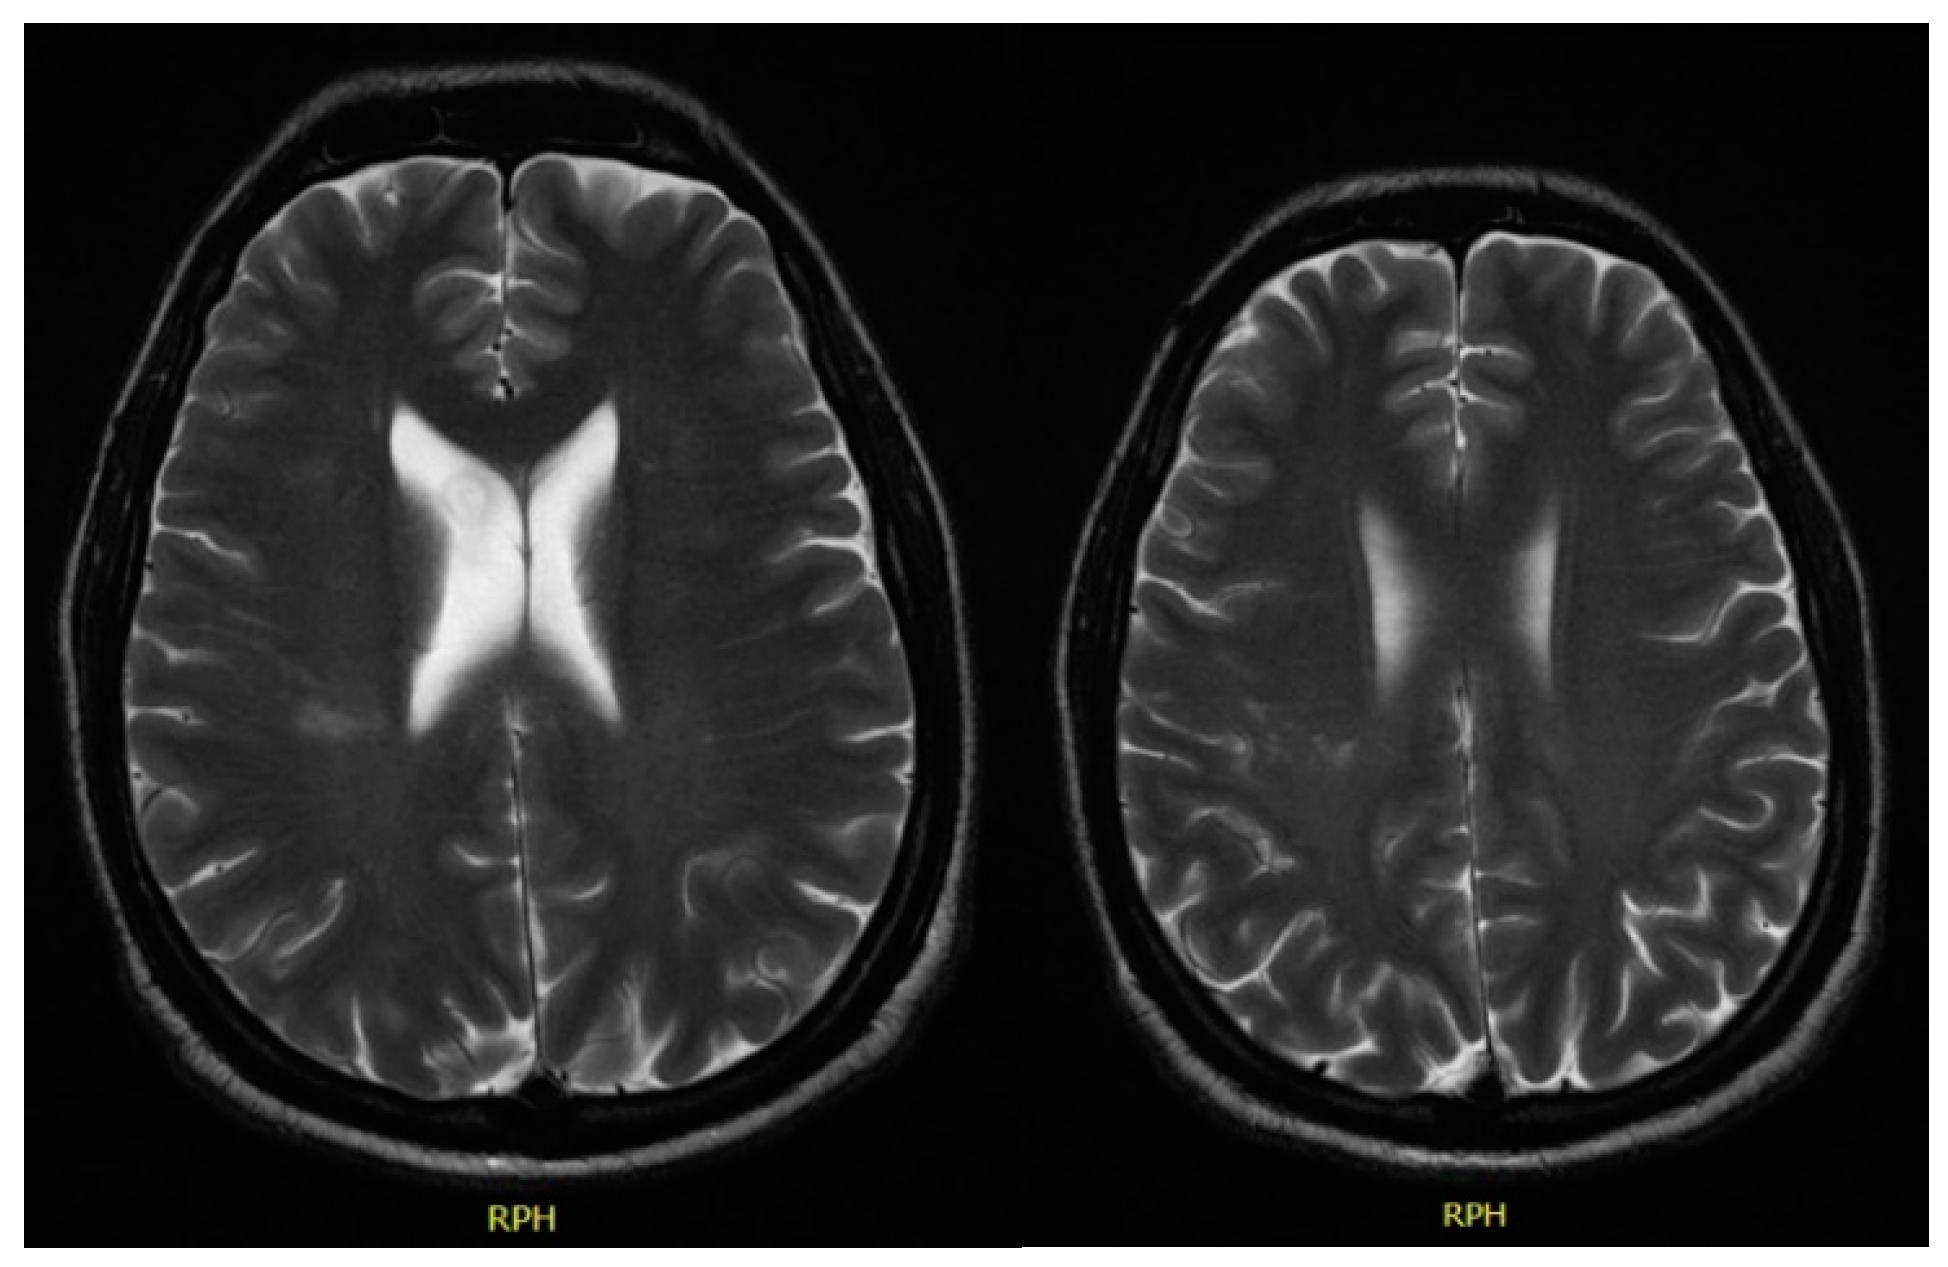

In December 2017, he was admitted to the emergency room with left central facial palsy and dysarthria. Cranioencephalic magnetic resonance showed an ischaemic lacunar lesion in the right corona radiate (Figure 1). Transoesophageal echocardiography (TEE) showed a prolapsed mitral valve, with suspected rupture of the anterior leaflet and severe regurgitation. Holter and ecodoppler of neck vessels were unremarkable. Blood analysis showed microcytic anaemia (haemoglobin 11.3 g/dL), with maintained leukocytosis of 11,000/μL and CRP of 10.2 mg/dL. A small vessel ischaemic disease was diagnosed. He was discharged and sent to cardiology and neurology appointments.

Figure 1. Cranioencephalic magnetic resonance with right ischaemic lacunar lesion in the corona radiata.